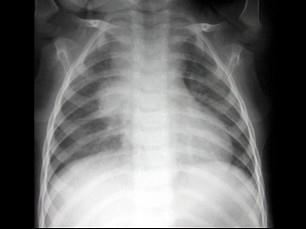

男,5岁,低热,盗汗,咳嗽2月余,结合图像,最可能的诊断是?(?)A.肺癌B.大叶性肺炎C.支气管肺炎D.肺结核E.过敏性肺炎

选项 A.肺癌 B.大叶性肺炎 C.支气管肺炎 D.肺结核 E.过敏性肺炎

答案 D